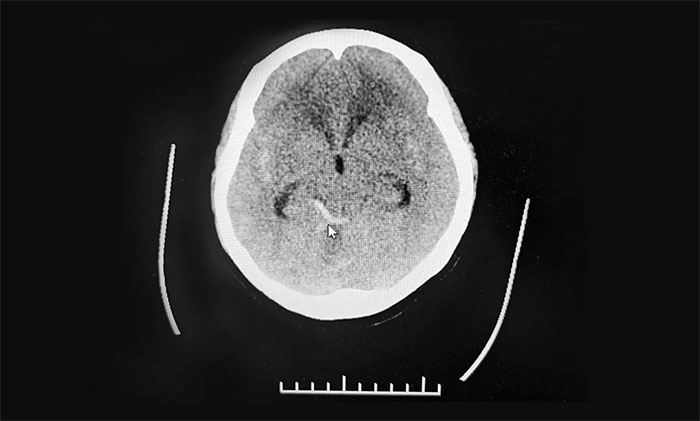

在神經(jīng)外科6A病區(qū)、急診科、麻醉科等多學(xué)科團(tuán)隊(duì)努力搶救下,患者意識(shí)蘇醒,恢復(fù)自主呼吸,生命體征均平穩(wěn)。醫(yī)護(hù)團(tuán)隊(duì)抓住時(shí)機(jī),遂立即轉(zhuǎn)影像科行頭顱CT,顯示蛛網(wǎng)膜下腔出血。做完CT檢查返回急診搶救室后,患者再次昏迷,并出現(xiàn)四肢抽搐癥狀,再次予以搶救。最終,患者意識(shí)終于恢復(fù)清醒,生命體征平穩(wěn),遂轉(zhuǎn)入神經(jīng)重癥監(jiān)護(hù)8A病房。

結(jié)合之前的核磁共振檢查,上海藍(lán)十字腦科醫(yī)院神經(jīng)外科學(xué)術(shù)副院長(zhǎng)、神經(jīng)外科6A病區(qū)主任于耀宇考慮,患者顱內(nèi)動(dòng)脈瘤破裂蛛網(wǎng)膜下腔出血并破入腦室。

▲ CT顯示蛛網(wǎng)膜下腔出血